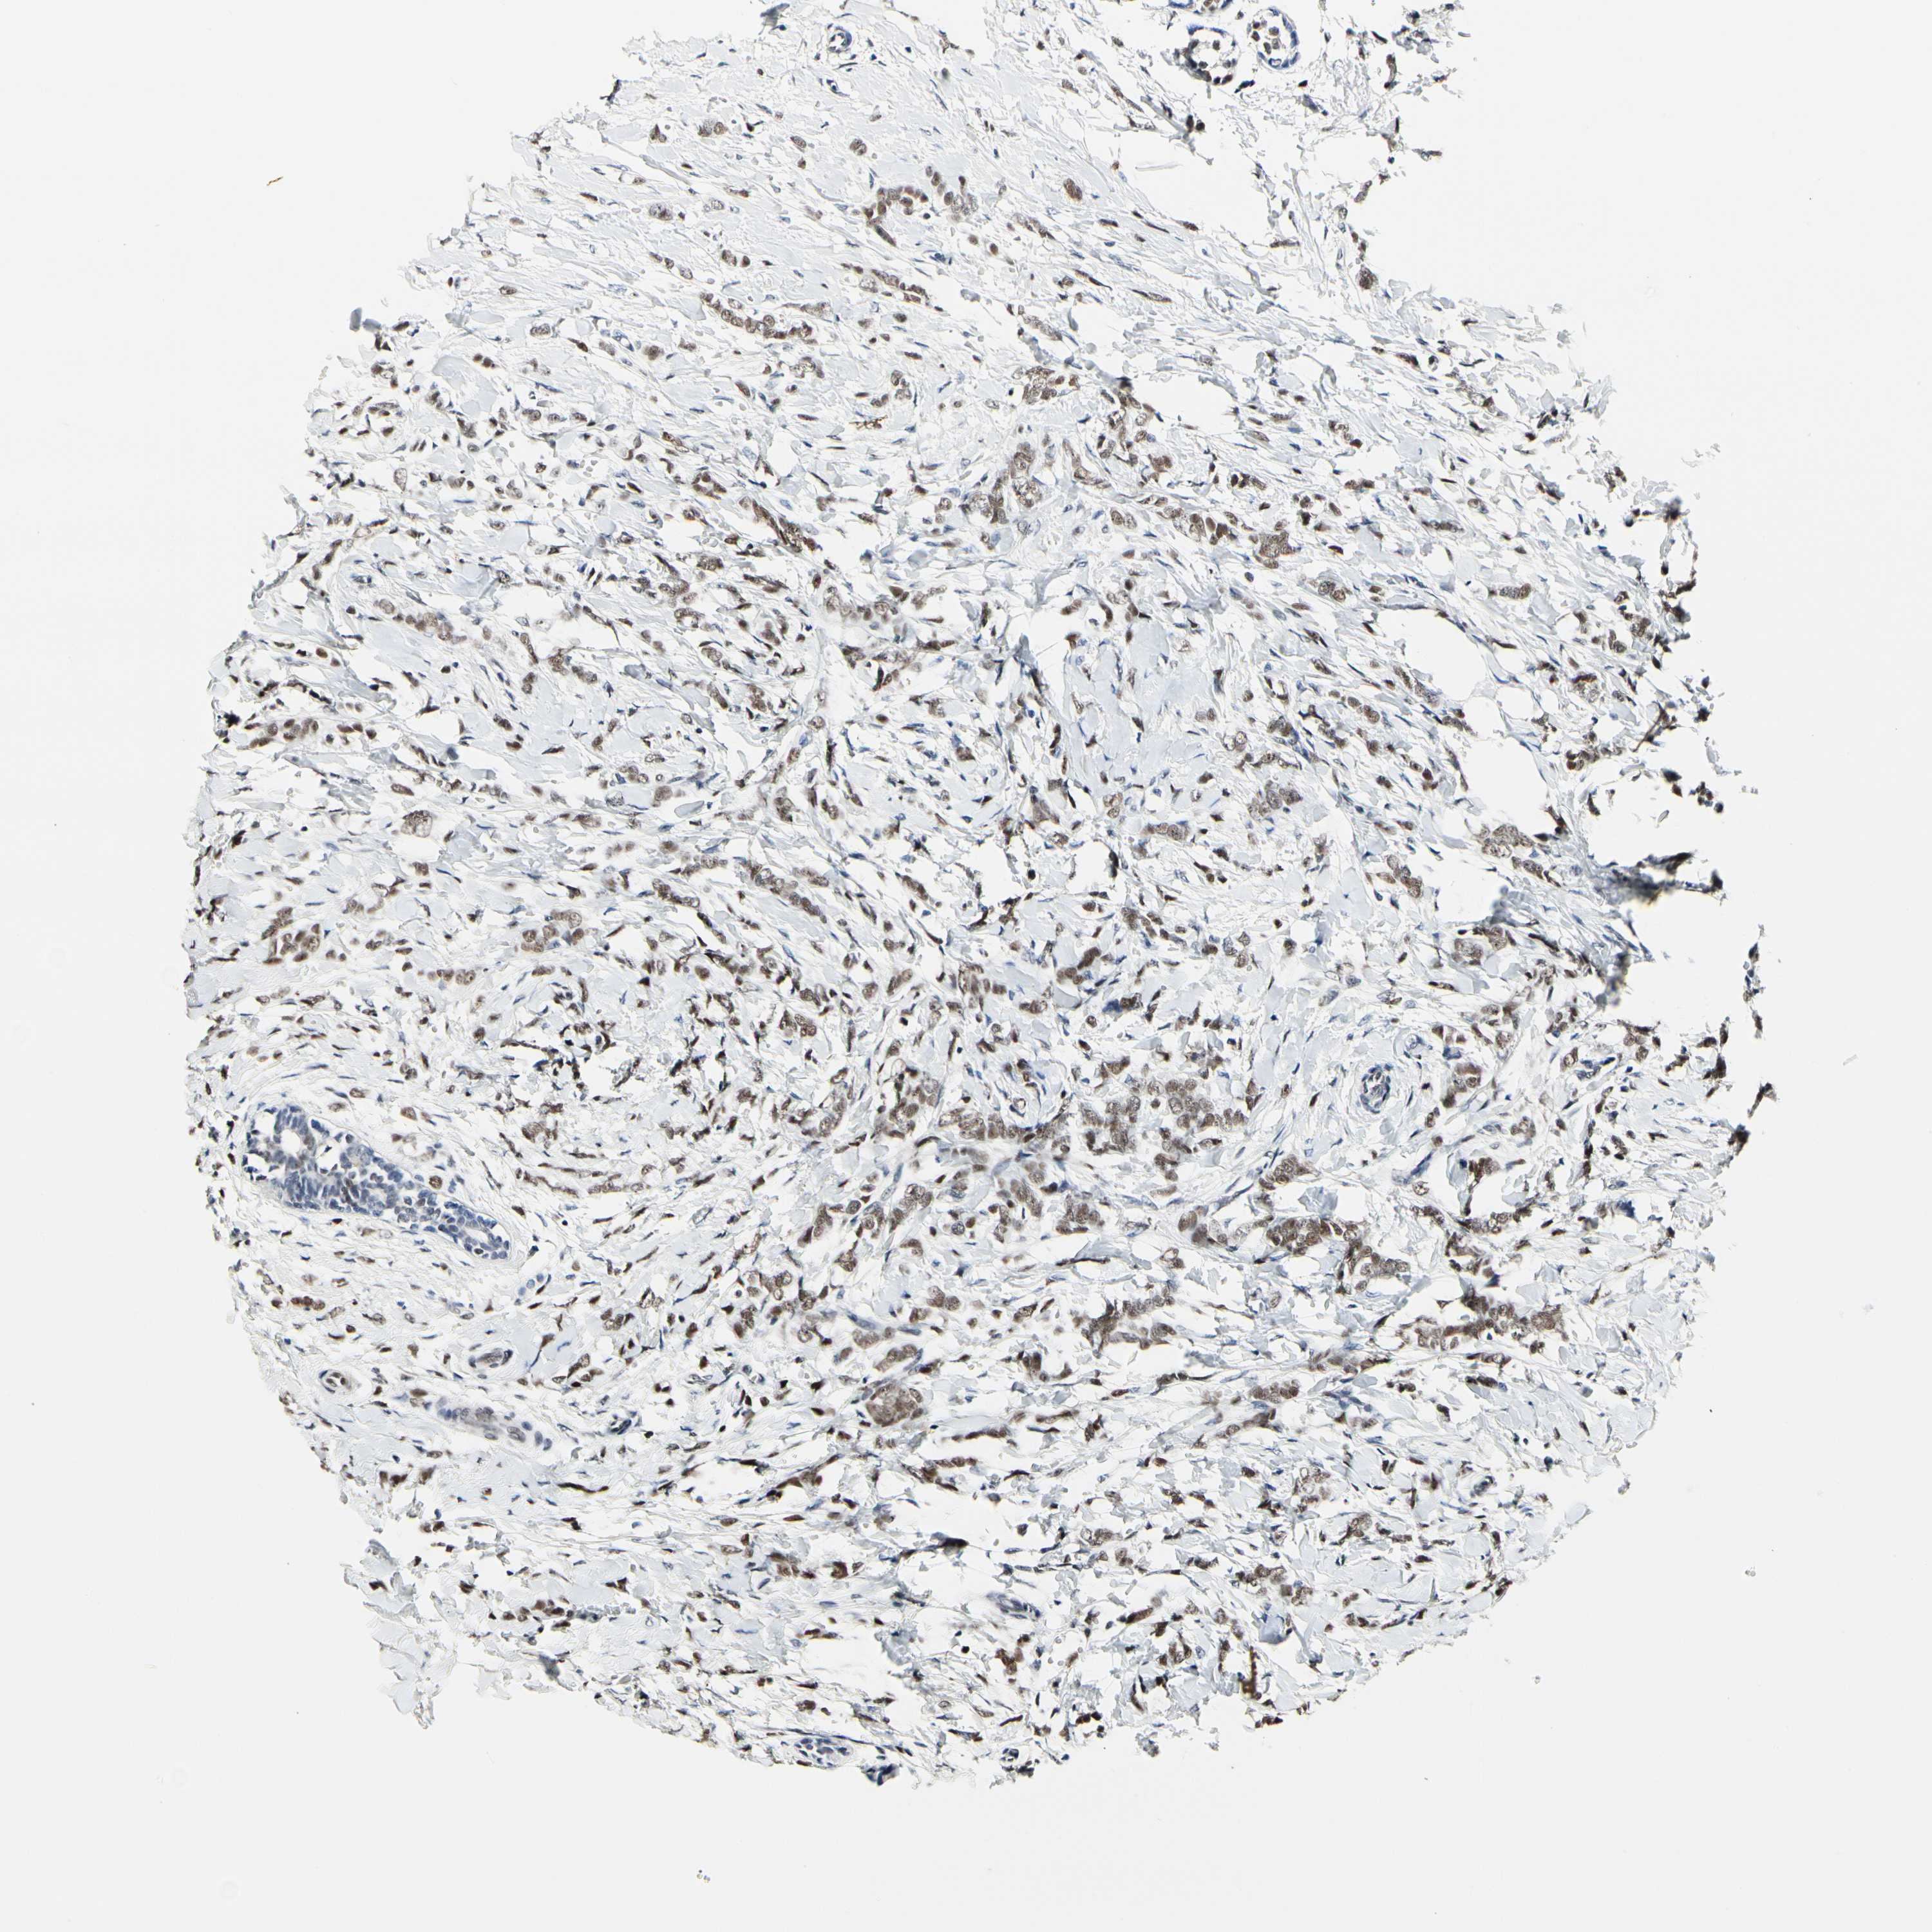

CANCER BREAST CANCER Show tissue menu

BRCA TCGA BRCA VALIDATION PROTEIN EXPRESSION